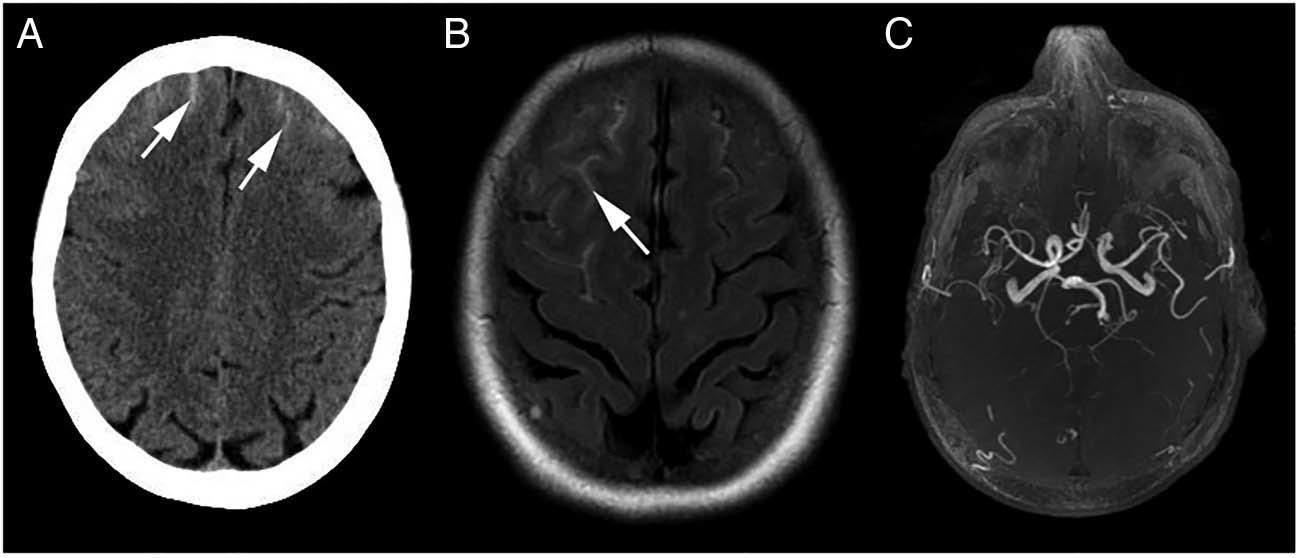

头颅平扫CT显示双侧额叶少量蛛网膜下腔出血(图1 A),但头颅CT未显示存在颅内动脉瘤。行头颅MRI检查,Flair像证实了蛛网膜下腔出血(图1 B),MRA检查显示正常(图1 C)。MRV排除了大静脉窦血栓形成的可能性(图2 A),而T1加权像证实了额叶皮层静脉血栓形成(图2 B,C)。给予患者肝素治疗后,患者头痛症状逐渐好转。

图1.平扫轴位头颅CT(A)显示双侧额上沟高信号(箭头所示),与蛛网膜下腔出血表现一致。Flair像(B)证实了蛛网膜下腔出血(箭头所示),右侧为著。MRA(C)显示Willis环正常,无动脉瘤证据